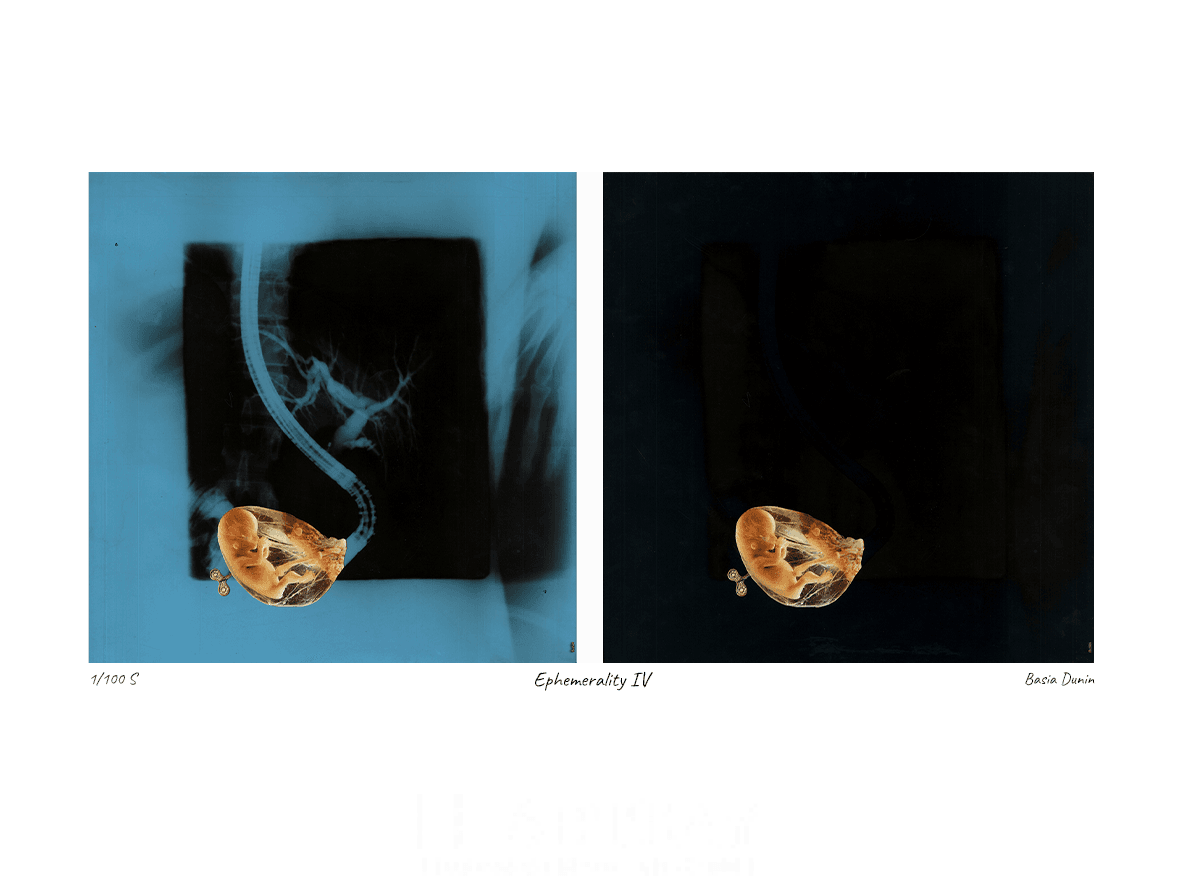

Ephemerality IV

Praca wykonana w technice kolażu, w kolorystyce czerni, niebieskiego oraz kontrastowej żółci.

| Rok wykonania: | 2021 |

| Technika: | Kolaż |